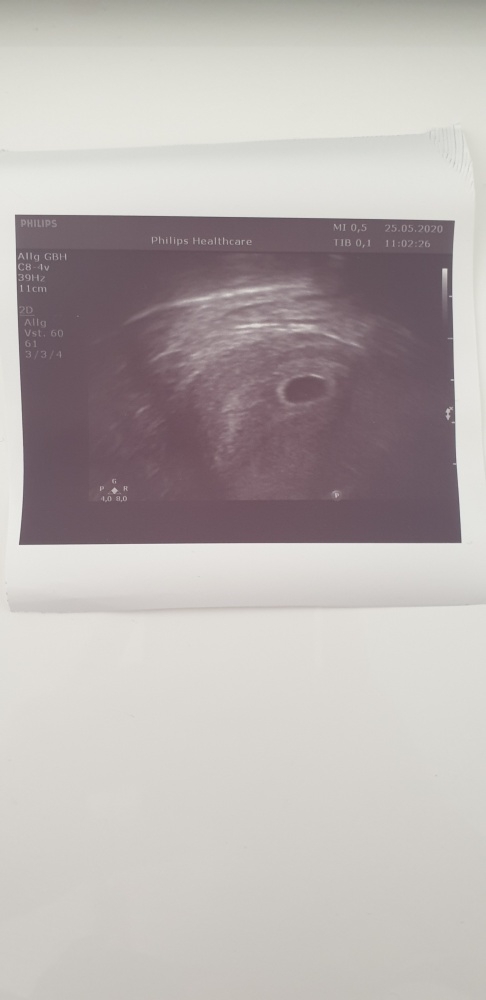

Im Schwangerschaft Forum im Bereich Schwangerschaft. Ssw und auf ultraschall ist nichts zu sehen. Ultraschallbild 41 SSW Ultraschall in der 5.

Aber es ist auch nicht ausgeschlossen dass es noch zu früh zum Nachweis ist. Daraufhin bin ich ins Krankenhaus gefahren um nachschauen zu lassen ob alles ok ist. Schwangerschaftswoche sieht man im Ultraschall nur einen kleinen schwarzen Punkt von weniger als einem Zentimeter Durchmesser.

Schwangerschaftswoche sieht man im Ultraschall nur einen kleinen schwarzen Punkt von weniger als einem Zentimeter Durchmesser. Die Übergänge sind natürlich fließend und auch die Messungen fallen unterschiedlich aus. Da hat man nur ein winziges schwarzes Pünktchen gesehen. Ultraschall in der 5. Eine Zyste hatte ich am Anfang auch 6 cm sogar. Februar und nachdem müsste ich mich ende der 6. Deshalb kann ich mir vorstellen dass man in der 5. Hallo ich hatte vor einem Jahr eine FG in der 8. Jetzt bin ich laut Urintest wieder schwanger aber auf dem Ultraschall war heute nichts zu sehenBin jetzt genau eine Woche überfällig.